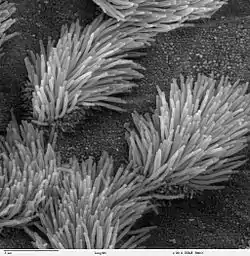

Ciliated epithelium in bronchus with short microvilli on non-ciliated cells | |

In the respiratory tract, from the trachea to the terminal bronchioles, the lining is of respiratory epithelium that is ciliated.[8] The cilia are hair-like, microtubular-based structures on the luminal surface of the epithelium. On each epithelial cell there are around 200 cilia that beat constantly at a rate of between 10 and 20 times per second.